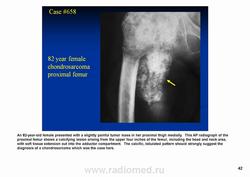

Рентгенологически выявляют в очаге деструкции участки обызвествления в виде крапчатости; кортикальный слой с признаками эрозии со стороны эндоста и истончения; размеры опухоли более 4 см; периостальная реакция слабо выражена или отсутствует; может наблюдаться деструкция кортикальной кости и наличие мягкотканного компонента; в длинных костях локализуется чаще в метафизах и диафизах; интенсивное внутрикостномозговое распространение.